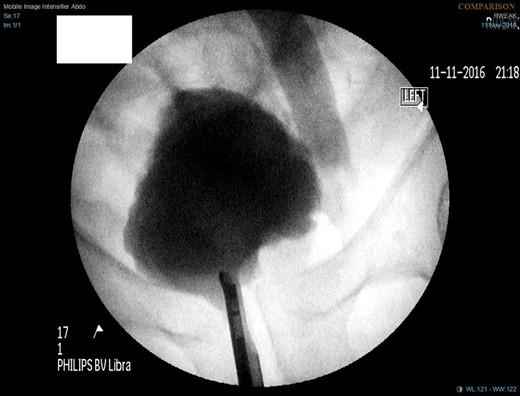

A week later, a left nephrostogram showed a capacious upper urinary tract with a deviated lower ureter which tapered in the pelvis with no filling defects seen above this level (Fig. 5). The appearances were in keeping with extrinsic compression. A week later, rigid cystoscopy, right-sided retrograde study, right JJ stent insertion and cystogram were performed. The left ureteric orifice could not be identified. The cystogram demonstrated no evidence of bladder herniation to the inguinal hernia (Fig. 6). Two months later, a non-contrast CT of the urinary tract demonstrated partial resolution of bilateral hydronephrosis, right-sided stent and left nephrostomy situated appropriately, persistence of left inguinoscrotal hernia and no other cause for ureteric compression. His eGFR was 34 mL/min when it was last checked a month prior to the non-contrast CT.